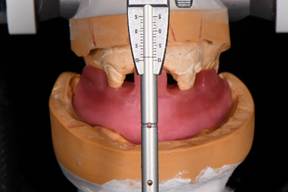

An open bite was taken. Heavy bodied puddy was mixed and rolled into a horseshoe shape and placed on the maxillary arch to key into the cuspids. Bite registration material was used on the base of the patty and the patient was instructed to lightly bite into the material (~1mm). The maxillary portion of the bite registration patty now cut back to have no hard or soft tissue contact. The patty was placed on the lower arch, and bite registration material was placed on the maxillary portion of the patty and the patient was instructed to lightly bite into the material (~1mm) (Fig. 3). A facebow record was obtained. Casts were mounted on and ARTEX (add full name).

Figure 3: Sequential bite registration